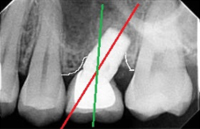

After thorough evaluation and diagnosis, which included Cone Beam CT scan, Digital Smile Design – DSD, 3D- intraoral Scanning etc, the treatment plan had been formulated.

Seven dental implants had been inserted using Digital Guided Placement Method. The surgical phase had been finalized with soft tissue grafting to insure proper gum seal around dental implants for long term success and to prevent peri-implantitis.